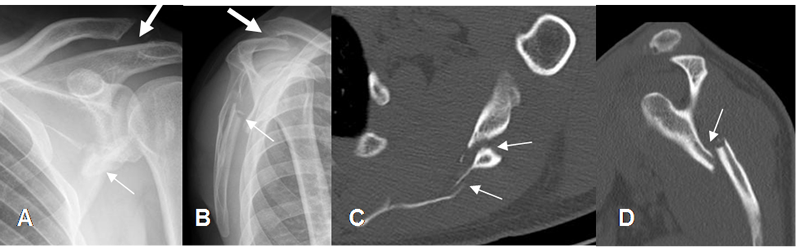

Fig 60. Fractura de escápula.

A: Rx AP de hombro, B: Rx lateral de escápula, C: TAC axial y D: TAC reconstrucción sagital. Fractura conminuta y cabalgada en el tercio medio de la escápula. (Flechas delgadas). En A y B, se aprecia luxación de la articulación acromioclavicular. (Flechas gruesas).